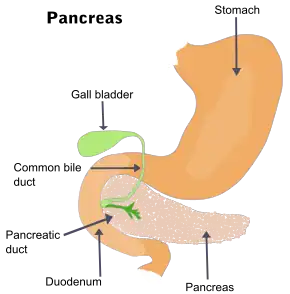

Acute pancreatitis (AP) is a sudden inflammation of the pancreas. Causes include a gallstone impacted in the common bile duct or the pancreatic duct, heavy alcohol use, systemic disease, trauma, elevated calcium levels, hypertriglyceridemia (with triglycerides usually being very elevated, over 1000 mg/dL), certain medications, hereditary causes and, in children, mumps. Acute pancreatitis may be a single event, it may be recurrent, or it may progress to chronic pancreatitis and/or pancreatic failure (the term pancreatic dysfunction includes cases of acute or chronic pancreatitis where the pancreas is measurably damaged, even if it has not failed).